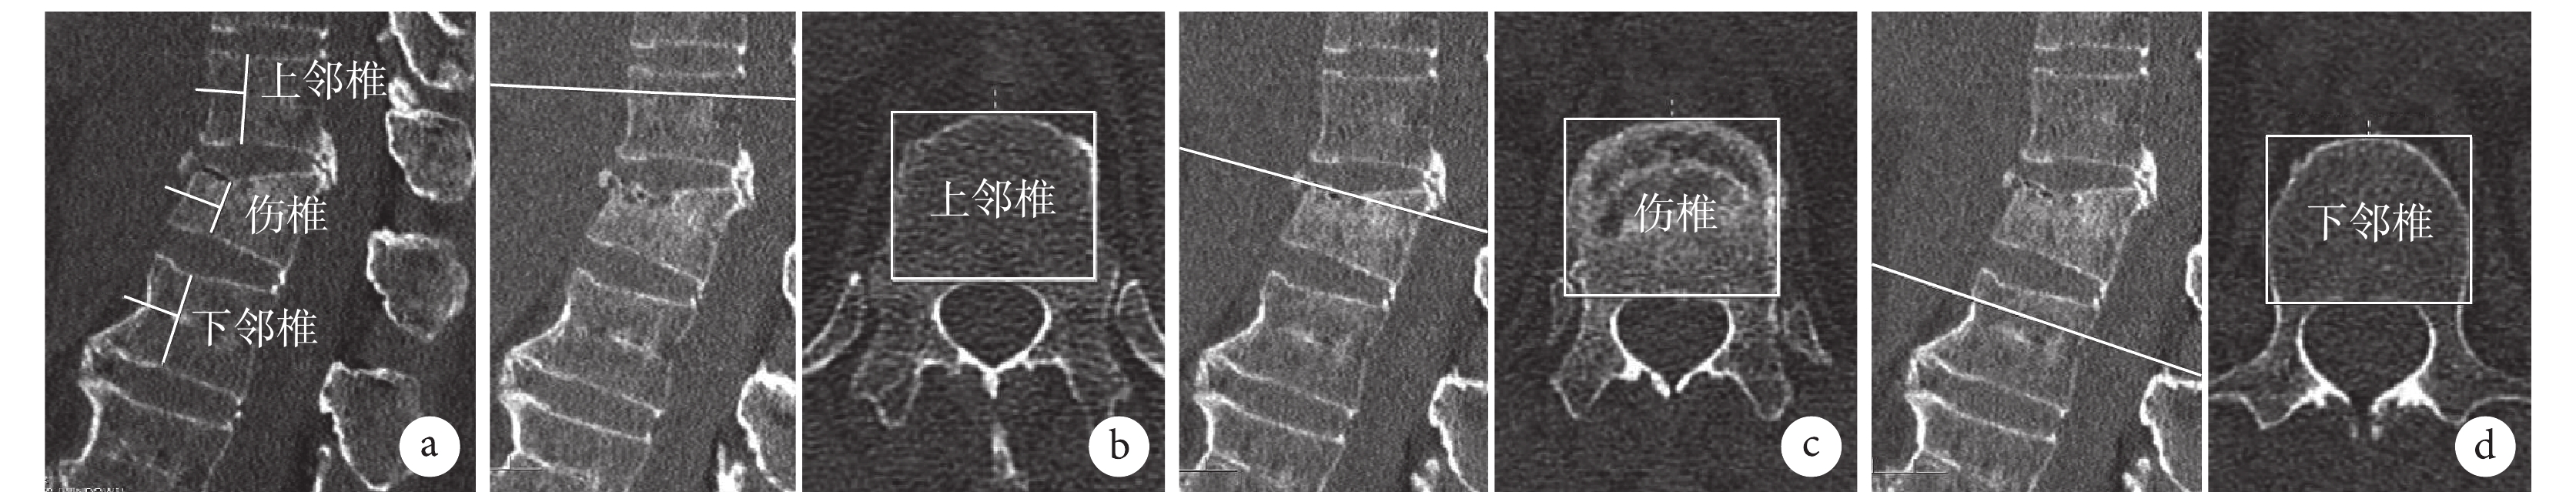

采用IMPACS軟件(東華軟件股份有限公司)測量。于術前CT測量傷椎椎體橫截面最大矩形面積(S1)、椎體正中矢狀位最低高度(H1),其中傷椎椎體橫截面最大矩形面積定義為在骨折累及的橫截面上以椎體前、后及左、右緣為邊界的矩形面積,取不同橫截面面積最大者。同時,測算傷椎上、下相鄰椎體對應橫截面最大矩形面積平均值(S2)和正中矢狀位高度平均值(H2)。計算傷椎標準椎體橫截面最大矩形面積S(S1/S2)、傷椎標準椎體正中矢狀位最低高度H(H1/H2),最終獲得傷椎標準S/H比值。見圖1。

a. 傷椎及上、下相鄰椎體正中矢狀位最低高度;b~d. 上鄰椎、傷椎及下鄰椎椎體橫截面矩形面積

Figure1. Measurement diagram of the standard S/H ratio of the injured vertebraa. The lowest sagittal height of the injured vertebra and the upper and lower adjacent vertebrae; b-d. Cross-sectional rectangular area of the upper adjacent vertebrae, injured vertebrae, and lower adjacent vertebrae